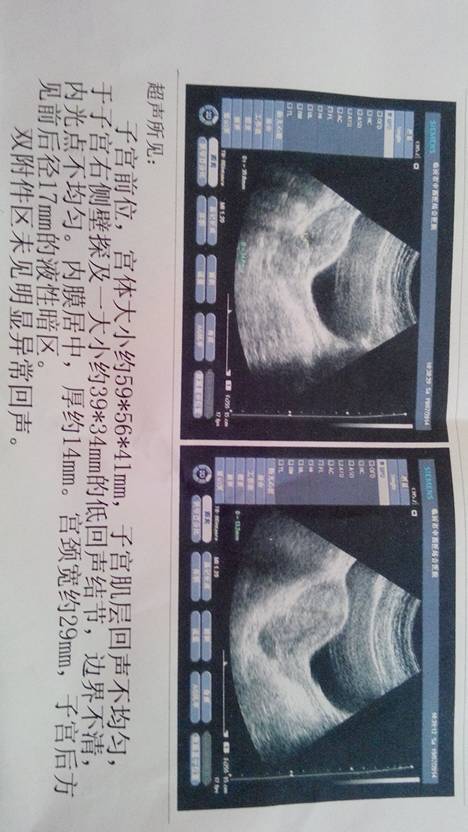

你好,这个报告单里没有显示有孕囊。肌层的低回声节结可能是一个小的肌瘤,这个大小不会有影响的,不必担心。 如果早孕试纸测试是阳性,没有其他异常,可以再等一周以后复查。因为排卵时间不是固定不变的,可能你只是排卵晚受孕晚而已。

这个数据的确还看不到,一次检查不能确定,没有出血就等一周后复查,正常都可以看到了,如果有出血,或非常担心,可隔天再抽血,对比HCG变化,就可以判断是否正常宫内孕。

一般不会的,不必担心。只要不剧烈腹痛,不出血,就没事,时间短本来就看不到,谁都是这样,再过几天就可以看到了。